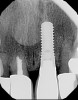

Fig 3. Pretreatment site-specific CBCT showing thick intact buccal plate and class 1 sagittal root position. Preplanning with a bone-level 4.1-mm diameter implant assured a 3-mm buccal gap upon placement and a screw-retained position.

Figure 3

Fig 4. Pretreatment site-specific CBCT showing thick intact buccal plate and class 1 sagittal root position. Preplanning with a bone-level 4.1-mm diameter implant assured a 3-mm buccal gap upon placement and a screw-retained position.

Figure 4

The patient, a healthy 45-year-old nonsmoking woman (American Society of Anesthesiologists [ASA] II), presented with a failed maxillary central incisor due to severe internal-external root resorption (Figure 1). She had a high esthetic risk profile based on 12 presenting esthetic risk factors (key No. 1), including a high lip line, high esthetic expectations, and adjacent teeth that had been restored (Figure 2).Site-specific CBCT (Carestream CS 9300, Carestream Dental, carestream.com) noted a thick intact buccal plate and a class 1 sagittal root position (Figure 3 and Figure 4). Preplanning with a bone-level 4.1-mm diameter x 14-mm long implant (Straumann Bone Level Roxolid® SLActive, Straumann, straumann.com) assured a 3-mm buccal gap upon placement and a screw-retained position (key No. 2). Prior to placement, intact buccal and palatal walls were confirmed. Figure 5 shows palatal wall placement of the implant after minimally traumatic flapless tooth extraction. An anatomically correct surgical guide template was used to assure a screw-retained position and correct vertical depth of approximately 4 mm from the mid-buccal apical extent of the guide template, which correlated to 1 mm apical of the intact buccal plate (key Nos. 3 through 5). The two-unit (8-9x cantilever) fixed provisional was recemented post-surgery. The 3-mm buccal gap was grafted tightly with a low-substitution DBBM (Bio-Oss®, Geistlich Pharma, geistlich-na.com) (key No. 6), and a pouch was created with a Buser membrane instrument (Hu-Friedy, hu-friedy.com) from line angle to line angle as a mini full-thickness flap to the mucogingival border to accept a connective tissue graft (Figure 6). The connective tissue graft, 1-mm thick x 12-mm long x 7-mm wide (Figure 7), was harvested from the palate (key No. 7).